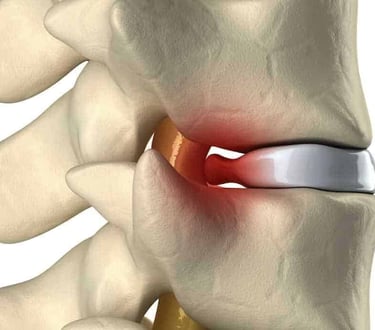

Cirugía de columna

Dolor de cuello

Dolor de espalda

Ciática

Hernia de disco

Cirugía mínimamente invasiva